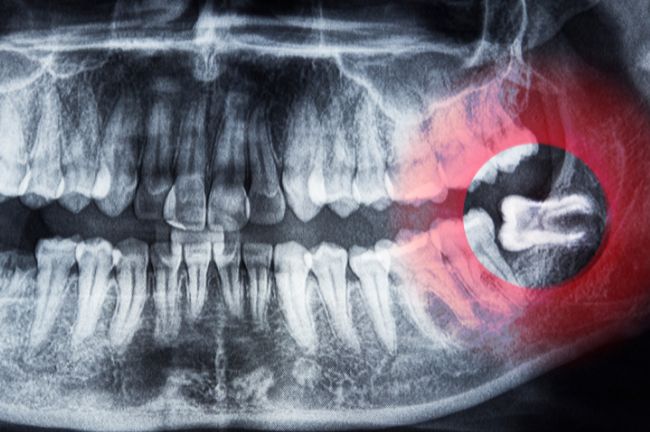

受診して親知らずをすぐに抜くことはありません。親知らずの生え方や歯根の状態を事前に確認するために、まずはレントゲン撮影を行います。

特に、下の親知らずは血管や神経に近い部分に生えていることがあるため、事前の確認が重要です。

親知らずは真っすぐ生えてくることが少なく、横向きや斜め向きに生えていたり、頭の一部しか出ていなかったりすることが多いです。

このように、本来とは異なる生え方をする親知らずは、歯みがきが難しく、プラークがたまりやすいです。その結果、他の永久歯と比べて虫歯や歯周病になるリスクが高まります。

親知らずが虫歯や歯周病になると、隣の健康な歯にも悪影響を与える可能性があります。最悪の場合、隣の歯も失う可能性があるため、注意が必要です。また、親知らずの周囲に細菌感染が起こると、智歯周囲炎になり、腫れや痛みの原因にもなります。

骨の中に埋まっている親知らずの周囲に含歯性嚢胞という膿の袋ができることがあります。一般的には無症状であり、虫歯や歯周病の治療でレントゲン撮影をした際に発見されることが多いです。

含歯性嚢胞を放置すると徐々に大きくなり、顎の骨を溶かす可能性があるため、早めに抜歯することが望ましいです。